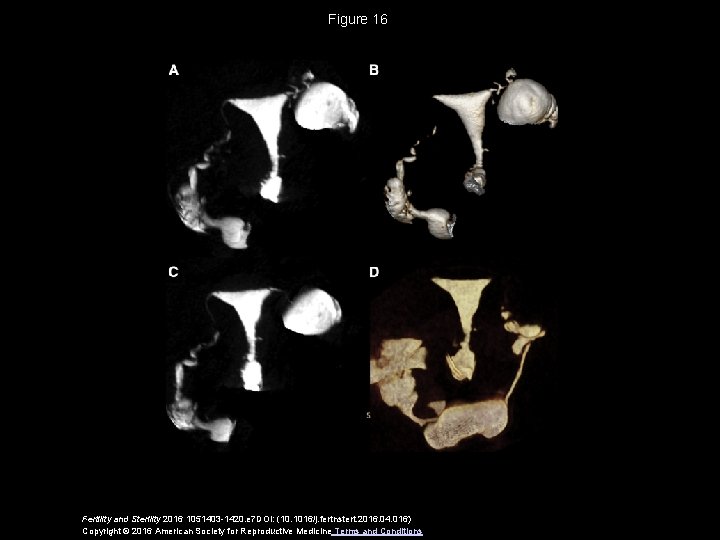

Figure 16 Fertility and Sterility 2016 1051403 -1420. e 7 DOI: (10. 1016/j. fertnstert. 2016. 04. 016) Copyright © 2016 American Society for Reproductive Medicine Terms and Conditions